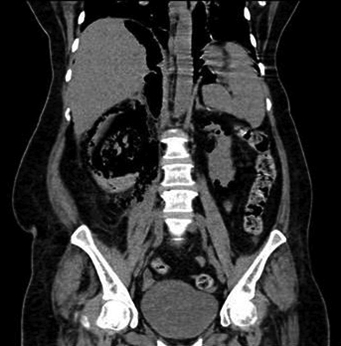

A 42-year-old female, known case of type 2 diabetic on oral hypoglycemic treatment for last two years, presented in emergency with acute left flank pain of four days duration. She had a history of low-grade fever for five days. On examination, her blood pressure was 130/90 mmHg and pulse rate was 100/minute with tenderness in her left flank region. On investigation, her Haemoglobin (Hb) was 9.1 gm/dl; Total Leukocyte Count (TLC), 18.6×103/μl with 87% neutrophils; platelet count, 2.36×105/μl, random blood sugar 545 mg/dl; serum acetone was absent, serum creatinine, 1.86 mg/dl and serum potassium 3.6 mEq/l. She was reactive for HIV-1 by ELISA and Western blot. A routine urine examination by dipstick showed trace albumin; microscopic examination revealed 40-42 pus cells/high power field and no organism was isolated on culture. Her blood culture was negative. Ultrasonography of abdomen showed features of Left Kidney (LK) Emphysematous Pyelonephritis (EPN). Computed Tomography (CT) [Table/Fig-1] showed an enlarged and oedematous left kidney with multiple pockets of air in the pelvicalyceal system, renal parenchyma, perinephric region and ureter, suggestive of EPN Class 3A. She was treated with intravenous antibiotics, insulin and Percutaneous Nephrostomy (PCN). However, PCN did not relieve her symptoms and an emergency nephrectomy of her LK was carried out on the next day. The specimen was sent for histopathological examination.

Multiple air collections in renal parenchyma and perinephric region suggestive of emphysematous pyelonephritis (computed tomography).